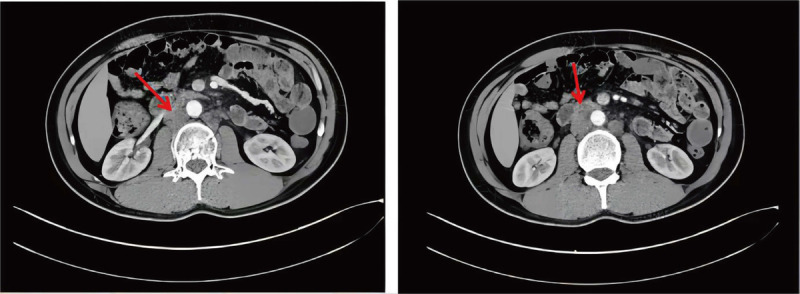

This case study demonstrates a single-position supine approach for robotic retroperitoneal lymph node dissection (R-RPLDN) for the treatment of nonseminomatous germ cell tumors and residual masses after chemotherapy. We performed a bilateral R-RPLDN in a 33-year-old man with nonseminomatous germ cell tumors and residual postchemotherapy masses. For this approach, the patient was placed in a steep Trendelenburg position, and a 5-port transperitoneal technique was used, with the robot docked so that the arms were oriented cephalad. This approach allowed simultaneous access to both sides of the retroperitoneum, thereby eliminating the need for bilateral lymphadenectomy and patient repositioning. Bilateral R-RPLDN was performed using a single-position supine approach. This versatile approach offers a less invasive, more efficient, and safer solution for removing residual postchemotherapy testicular cancer masses.